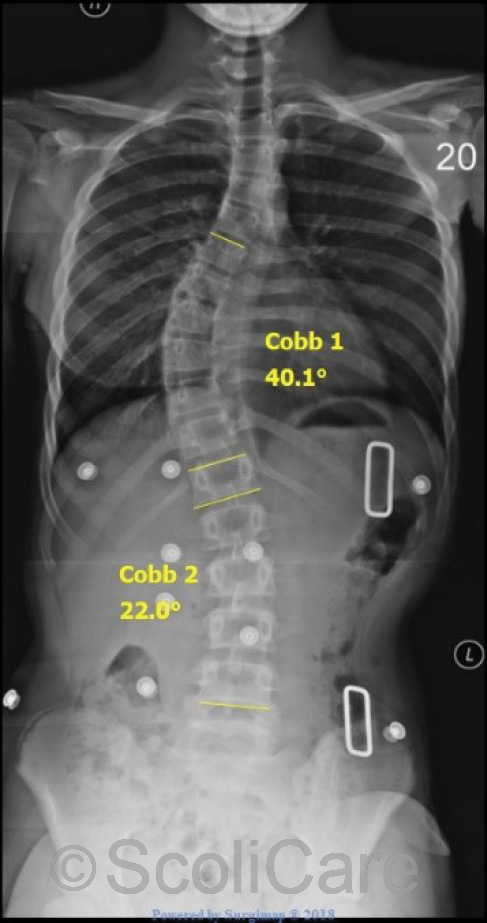

The patient’s spine responded favourably to the treatment with one-month x-rays showing that the larger curve could be reduced from 71° down to 40° with the patient wearing the brace (Figure 3). In total, the patient was braced for 18 months. The patient also participated in supervised exercise sessions at the clinic and performed similar exercises at home.

Figure 2: In-brace frontal x-rays taken one

month after the brace fitting.